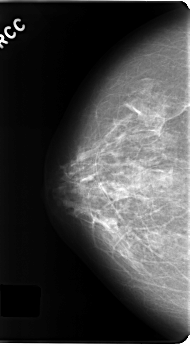

C_0191_1.RIGHT_CC

RIGHT_CC LINES 4832 PIXELS_PER_LINE 2648 BITS_PER_PIXEL 12 RESOLUTION 50 NON_OVERLAY